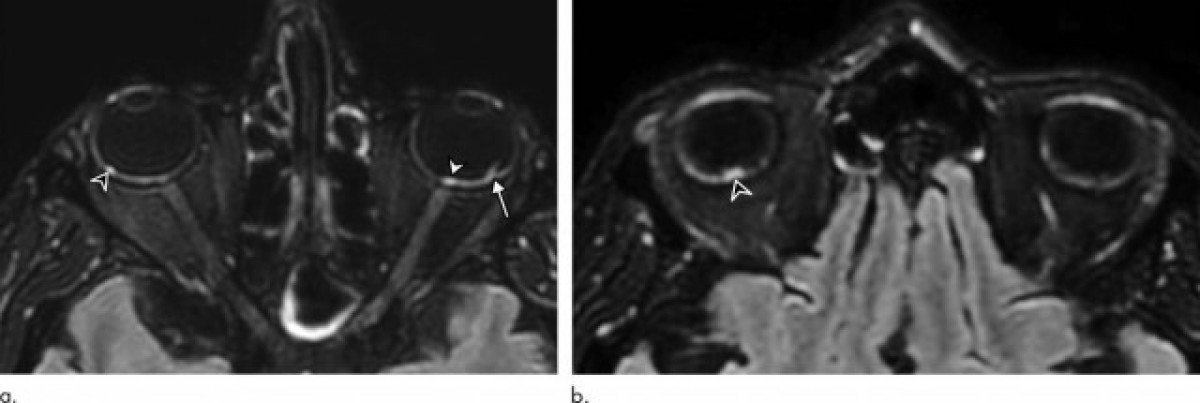

Dels 129 pacients, nou (7%) tenien troballes anormals en la ressonància magnètica del globus ocular. Les ressonàncies magnètiques van mostrar un o més nòduls a la part posterior, o pol posterior, del globus ocular. Vuit dels nou pacients havien passat un temps a la unitat de cures intensives (UCI) per COVID-19.

"Vam demostrar que alguns pacients amb COVID-19 greu de la cohort francesa de COVID-19 tenien un o diversos nòduls en el pol posterior del globus --destaca l'autor principal de l'estudi, Augustin Lecler, professor associat de la Universitat de París i neuroradiòleg del Departament de Neuroradiologia de l'Hospital Fundació Adolphe de Rothschild de París-. Aquesta és la primera vegada que es descriuen aquestes troballes mitjançant ressonància magnètica ".

Els nou pacients tenien nòduls a la regió macular, l'àrea a la part posterior de l'ull responsable de la nostra visió central. Vuit tenien nòduls en els dos ulls.